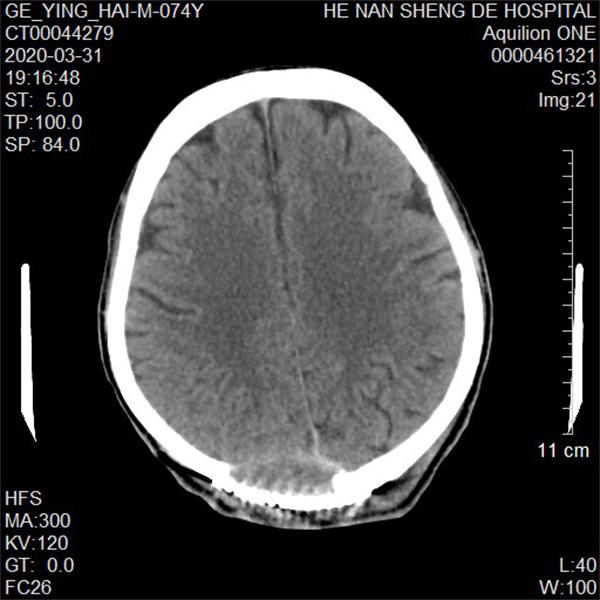

术后复查CT影像结果视图